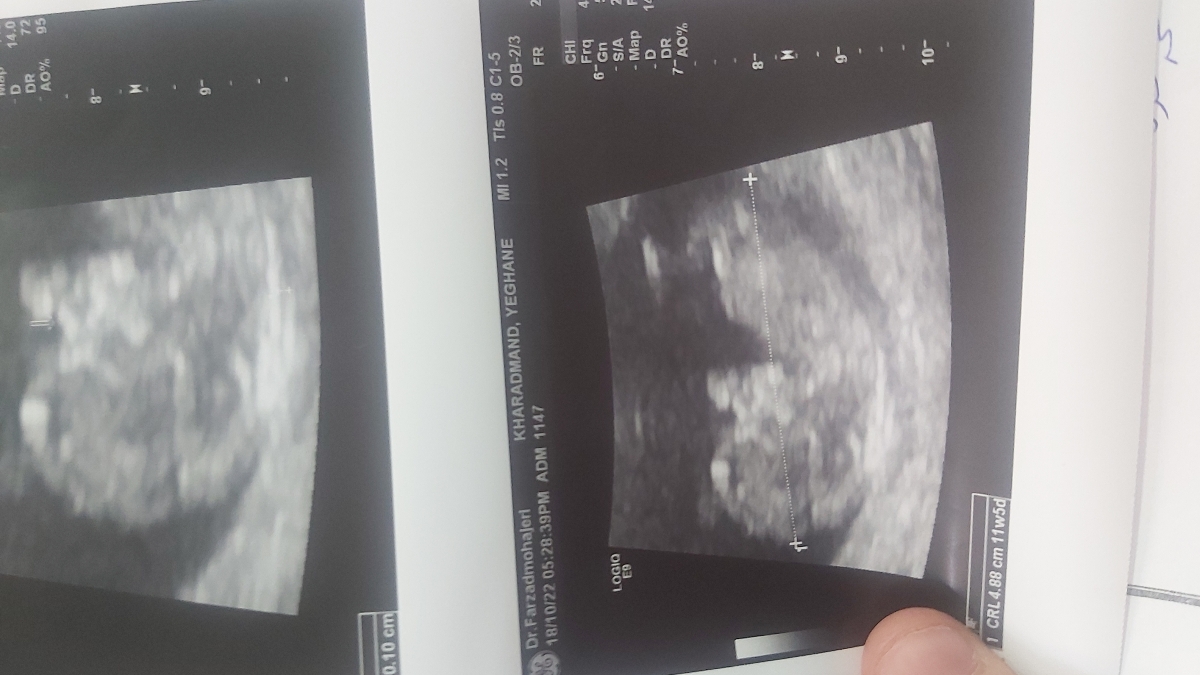

جواب سونو انتی منه ک رفتم ...طول سرویکسم ننوشته چرا دکتر ؟

از روی جمجمه میشه جنسیتش بهم بگید؟

برخی مراکز سونوگرافی نمی نویسند تاکید کنید در هفته 18 و زمان سونوگرافی آنومالی اسکن طول سرویکس کنترل شود،، موقعیت جفت را نگفتند چون من در گزارش نمیبینم. در مورد جنسیت هم منتظر سونوگرافی آنومالی اسکن باشید گل من

فوندال و قدامی هستش خانم دکتر

بسیار هم عالی نازنینم ، موقعیت جفت هم خوب است❤️